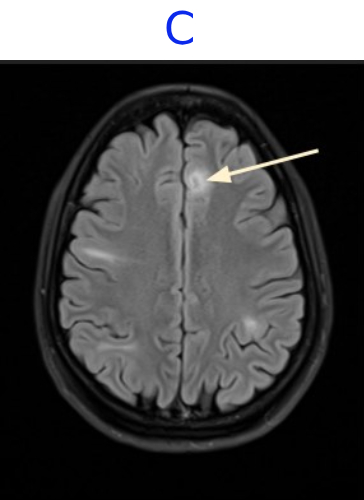

• C. MR BRAIN

• C. Areas of mild cortical thickening and blurring of the gray–white junction, consistent with focal cortical dysplasia